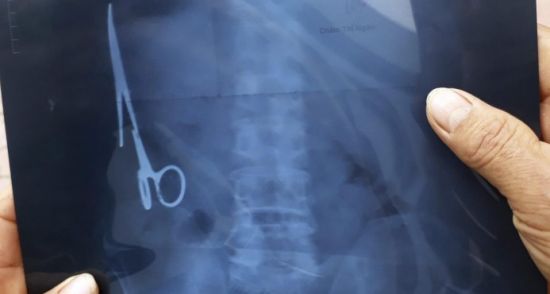

Çekilen röntgen kurtuluşu oldu

54 yaşındaki Vietnamlı, geçen ay bir kaza daha geçirince hastaneye gitti. Çekilen röntgen 18 yıllık gizemi aydınlattı. Nhat'ın midesinde 15 santimlik bir makas vardı. Nhat, yıllar önce midesinde unutulan makastan kurtulmak için yeniden biçak altına yattı.